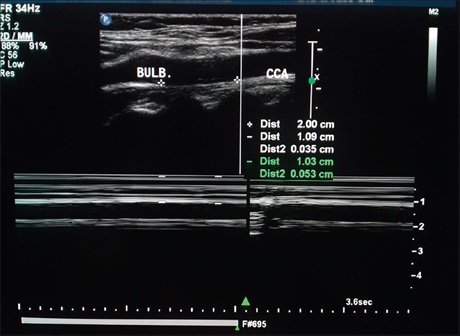

Further observations on the “spaghetti sign” in upper urinary tract hemorrhage

Prof. Funsho Komolafe, Sabir Hussain, Syed Waqar Hussain (Author)

136-140